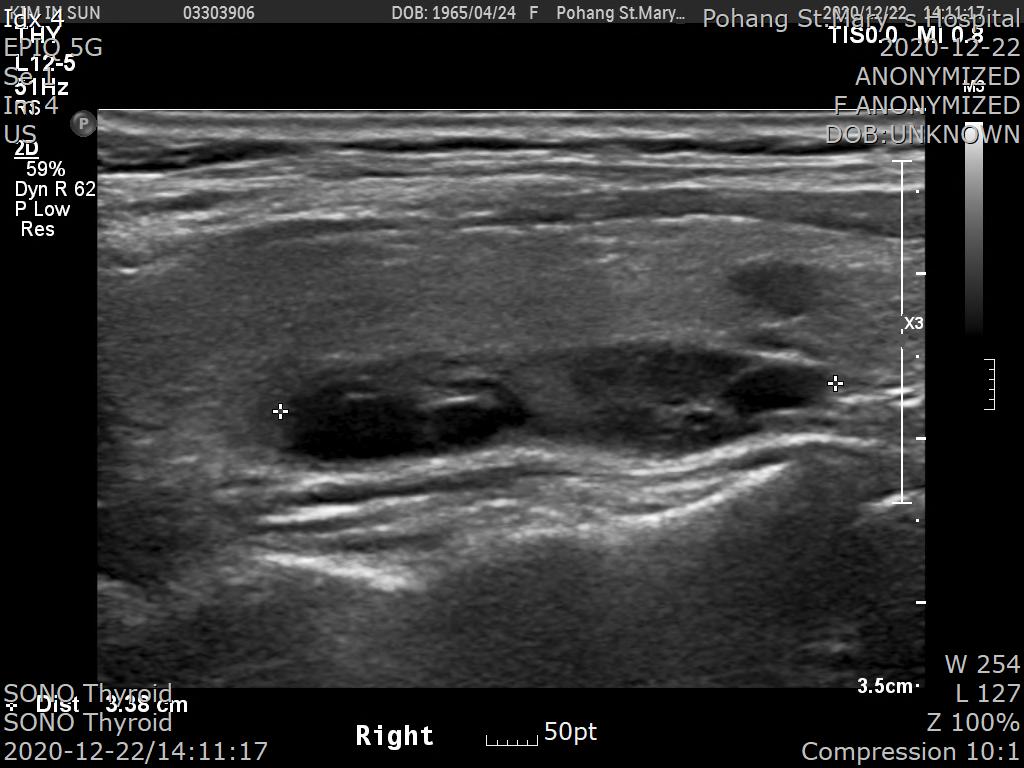

2020.12.21일 제 외래로 오셔서 초음파를 시행했습니다.

[경부초음파 판독]

About 3.5 cm lengthed elongated cystic lesion, inferior to right thyroid

; R/O Parathyroid nodule

; FNA was done.

REC) Check PTH and calcium level

우측 갑상선 뒤쪽으로 약 3.5cm 길이의 종양이 발견되었고 부갑상선 종양이 의심된다는 소견입니다.